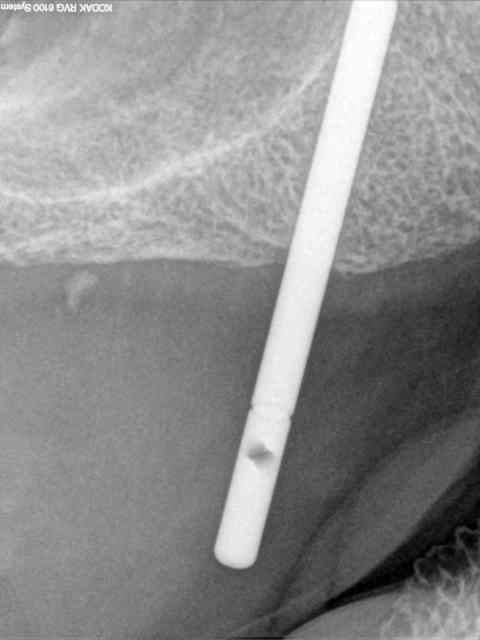

je vous mets les radios per-op.

secteur 1:

à l'aide du guide je détermine la position et l'axe de l'implant.

retrait du guide et contrôle radio puis pose des implants

17/02/2013 à 12h11

secteur 2:

on voit bien ici que cette méthode reste suffisamment précise pour longer le sinus sans le pénétrer.

je n'en demande pas d'avantage.

dentiste57 écrivait:

--------------------

> secteur 2:

> on voit bien ici que cette méthode reste suffisamment précise pour longer le

> sinus sans le pénétrer.

> je n'en demande pas d'avantage.

Cet implant pénètre de 5 à 6 mm dans le sinus.